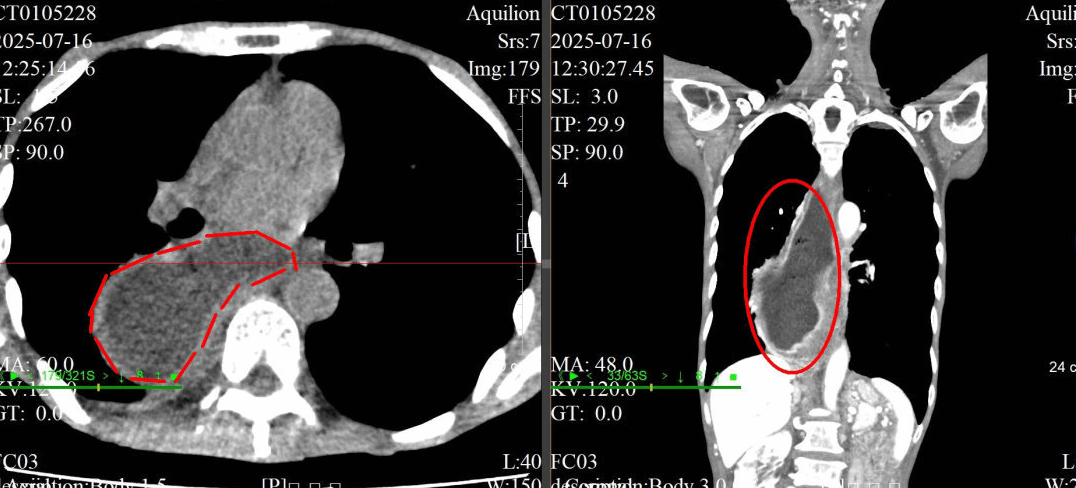

十年抗瘤路终迎破茧——多学科护航患者重获健康

25cm巨大肿瘤盘踞盆腔,十年间历经3次手术与化疗,恐惧让她一度犹豫就医......近日,第五附属医院妇科刘芳主任团队,联合普通外科、麻醉科等多学科力量,成功为一名复发性卵巢交界性肿瘤患者实施高难度手术,完整切除肿瘤并完成全面分期手术,助其摆脱十余年病痛阴霾,重获健康新生。十年抗争,肿瘤再度来袭患者与卵巢交界性肿瘤的搏斗已长达十余年。期间,她经历了3次手术和化疗,承受…